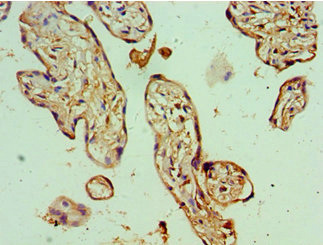

Immunohistochemistry of paraffin-embedded human placenta tissue using CSB-PA854079ESR1HU at dilution of 1:100